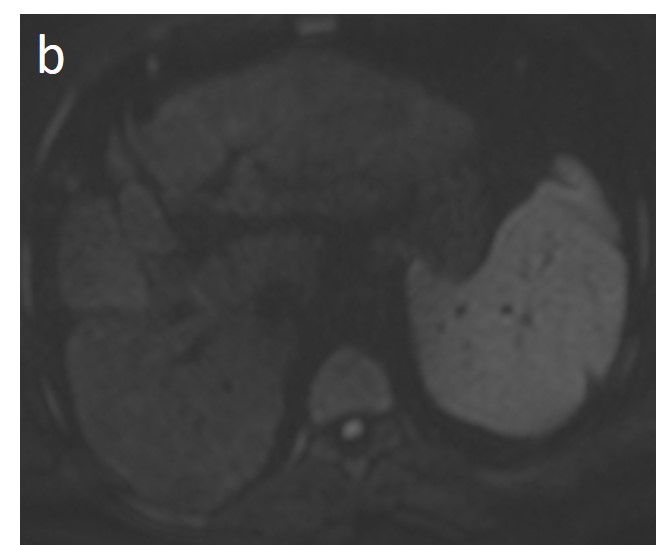

As mentioned before, the radiological hallmark that enables a confident non-histological diagnosis of HCC is the combination of hypervascularity on the arterial phase and hypoperfusion on the portal phase; as with CT, this “wash-in/wash-out” pattern is indispensable on MRI as well. According to the LI-RADS criteria, no lesion without hyperenhancement on the arterial phase can be definitely characterized as HCC; hyperenhancement has to be “non-rim”, i.e., not predominantly peripheral (in order to differentiate from metastases or cholangiocarcinoma) [51]. However, up to 40% of HCCs show no hypervascularity on the arterial phase, and these mainly represent early or poorly-differentiated HCCs [131,132]. Moreover, 40–60% of small HCCs lack wash-out during the portal phase [133,134] (Figure 10). Additional major and ancillary features are employed to help characterize the lesion and assign a LI-RADS category to it.

Figure 10. Evolution of a cirrhotic nodule into HCC. No suspicious lesions are identified on the T2 (a) and DWI (b) sequence of this 66-year-old man with cirrhosis due to hepatitis B infection. On the follow-up scan, performed 3 months later, increased T2 signal (c) is now observed in a nodule in segment V, which is associated with diffusion restriction (arrow) (d). After contrast administration, arterial enhancements (e) without delayed wash-out (f) are seen; absence of wash-out is frequent in early HCCs.